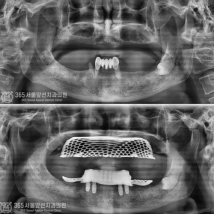

디지털 기술로 더 정확하고 확실하게

디지털(스마트) 임플란트

디지털 스캐닝 기술을 이용해 정교한 3D 모델을 만들고

임플란트의 정확한 위치에 식립하여 높은 정밀도와 맞춤형 치료를 제공합니다.

평균 악당 30분의 빠른 식립시간, 치료 케이스 다수 보유

전체 임플란트

상·하악 전체 치아를 대체하는 임플란트로 최소한의 식립을 통해

자연치아와 비슷한 기능을 수행할 수 있도록 합니다.